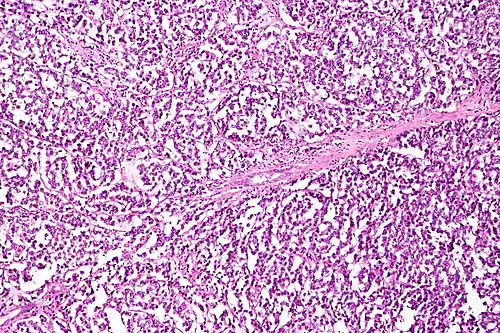

Das Dysgerminom (Syn.: Seminom des Ovars) ist ein maligner Tumor des Ovars und gehört zu den malignen Keimzelltumoren der Frau. Dysgerminome sind üblicherweise hormonell inaktiv. Der Tumor besteht aus undifferenzierten Keimzellen und wächst schnell.